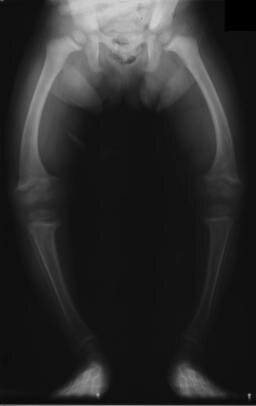

Wady postawy to odchylenia od prawidłowej sylwetki dotyczące najczęściej budowy kręgosłupa, klatki piersiowej i kończyn.

Najczęściej występującymi są: plecy okrągłeplecy okrągłe (nadmierna kifoza), plecy wklęsłeplecy wklęsłe nadmierna lordoza), skoliozaskolioza (boczne skrzywienie kręgosłupa) i płaskostopiepłaskostopie.

Plecy okrągłe, plecy wklęsłe i skolioza są wadami w budowie kręgosłupa.

Krzywica jest chorobą wieku dziecięcego, polegającą na nieprawidłowej mineralizacji kości i ich deformacji.

Schorzenie to powoduje poważne zmiany w układzie kostnym. Mogą one nie tylko utrudniać sprawne poruszanie się, ale także – w przypadku deformacji kości klatki piersiowej – wpływać na zaburzenia oddychania. Ponadto krzywicy często towarzyszy opóźnienie rozwoju psychoruchowego i skłonność do zakażeń.